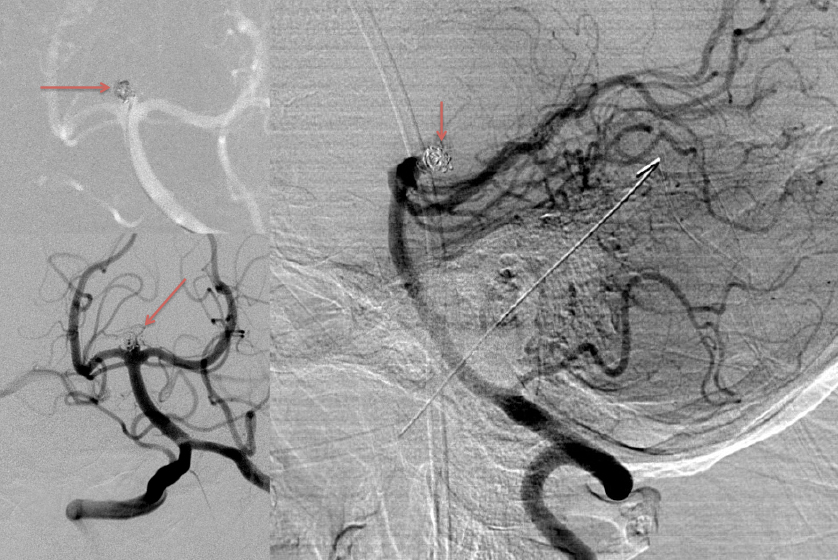

Urgent Cerebral Angiography confirmed a 5 mm posteriorly projecting aneurysm of the Basilar Artery Apex (Figure 2 A, B). Based on the location, morphology, and posterior projection, we decided to proceed to coil embolization of this high-risk aneurysm to prevent catastrophic re-bleeding and afford us the opportunity to maximize critical care for this patient during his hospital course. In this aneurysm, the dome-neck ratio was favorable from primary coiling, which was successfully performed resulting in near-complete embolization of the aneurysm (Figure 3 A, B). After 2 weeks of continued critical current l, endovascular, and neurosurgical care for complications of subarachnoid hemorrhage, including vasospasm and hydrocephalous, he was able to make a complete recovery and ultimately discharged home to complete his recovery, having regained all neurologic functions and activities of independent daily living and planning a return to work as an executive professional in the near future.

Figure 3: A) Initial Coil placement in Aneurysm dome B) Final AP and C) Lateral DSA demonstrating near complete obliteration of the ruptured aneurysm